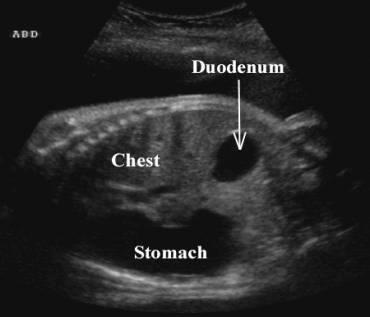

Duodenal atresia

What is the sonographic appearance of duodenal atresia?

Double bubble

polyhydramnios

Duodenal atresia

Double bubble

When can duodenal atresia be seen?